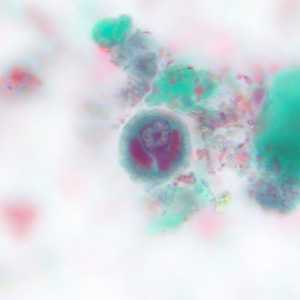

A 32-year-old Latin American man sought medical attention for persistent fever and cough. A sputum specimen was collected for testing. Smears were prepared and stained with Giemsa.